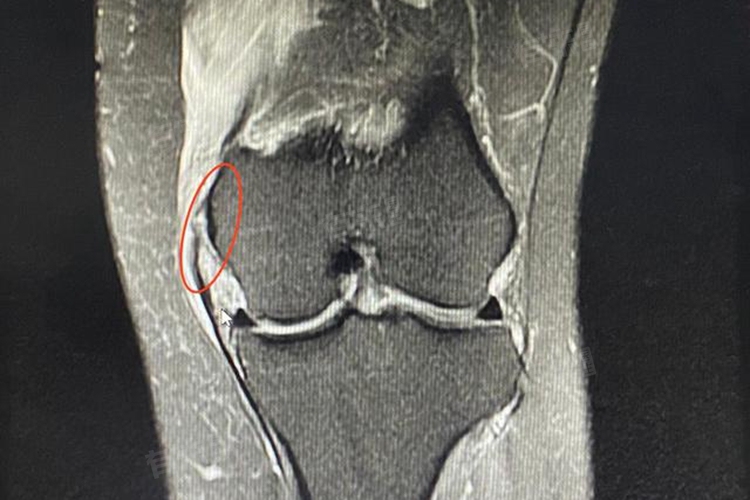

- 对于一些细微的软组织损伤或关节内部结构问题,磁共振成像检查更为精准。能够清晰显示内侧副韧带、半月板、滑膜、软骨等软组织的形态和结构,准确判断是否存在损伤及其程度。若怀疑是全身性疾病导致的疼痛,如风湿性关节炎,可能还需要进行实验室检查,包括血常规、血沉、C反应蛋白、抗链球菌溶血素“O”等指标检测,以辅助诊断疾病类型。

3、半月板内侧损伤:半月板内侧部分在膝关节运动中承担着缓冲和稳定关节的重要职责。在屈膝状态下,若膝关节突然扭转或受到较大压力,内侧半月板易遭受损伤。例如,在进行一些需要频繁扭转膝盖的运动时,内侧半月板可能因过度挤压、研磨而撕裂。损伤后的半月板无法正常发挥功能,在膝关节活动过程中,损伤部位与周围组织摩擦、撞击,从而导致左膝盖内侧突发疼痛,尤其在负重或扭转膝关节时疼痛更为显著。

1、内侧副韧带损伤:内侧副韧带位于膝关节内侧,连接股骨与胫骨,主要作用是防止膝关节外翻。当膝关节受到来自外侧的暴力冲击,或突然的扭转、过度伸展等异常动作时,内侧副韧带可能承受过大应力而受损。损伤发生时,韧带纤维部分或完全断裂,周围组织出现充血、水肿,刺激神经末梢,引发剧烈疼痛。患者往往能清晰感知疼痛来自膝盖内侧,且在膝关节屈伸或内外翻活动时,疼痛加剧。